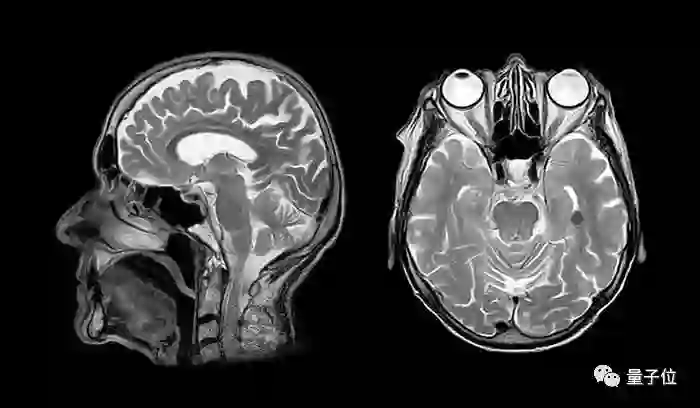

在美国,有将近五百万人拥有医学影像相关数据。这些数据包括 CT ,核磁共振和X光片等相关图像及诊断报告。

除此之外,这些影像往往附带患者的个人信息,以及就诊医生、医院、病史等诊疗流信息。这些信息不但涉及隐私,还事关患者的生命安全。因此,这些信息需要严密的保护。

医学影像是指为了医疗或医学研究,对人体或人体某部分,以非侵入方式取得内部组织影像的技术与处理过程,是一种逆问题的推论演算,即成因(活体组织的特性)是经由结果(观测影像信号)反推而来。